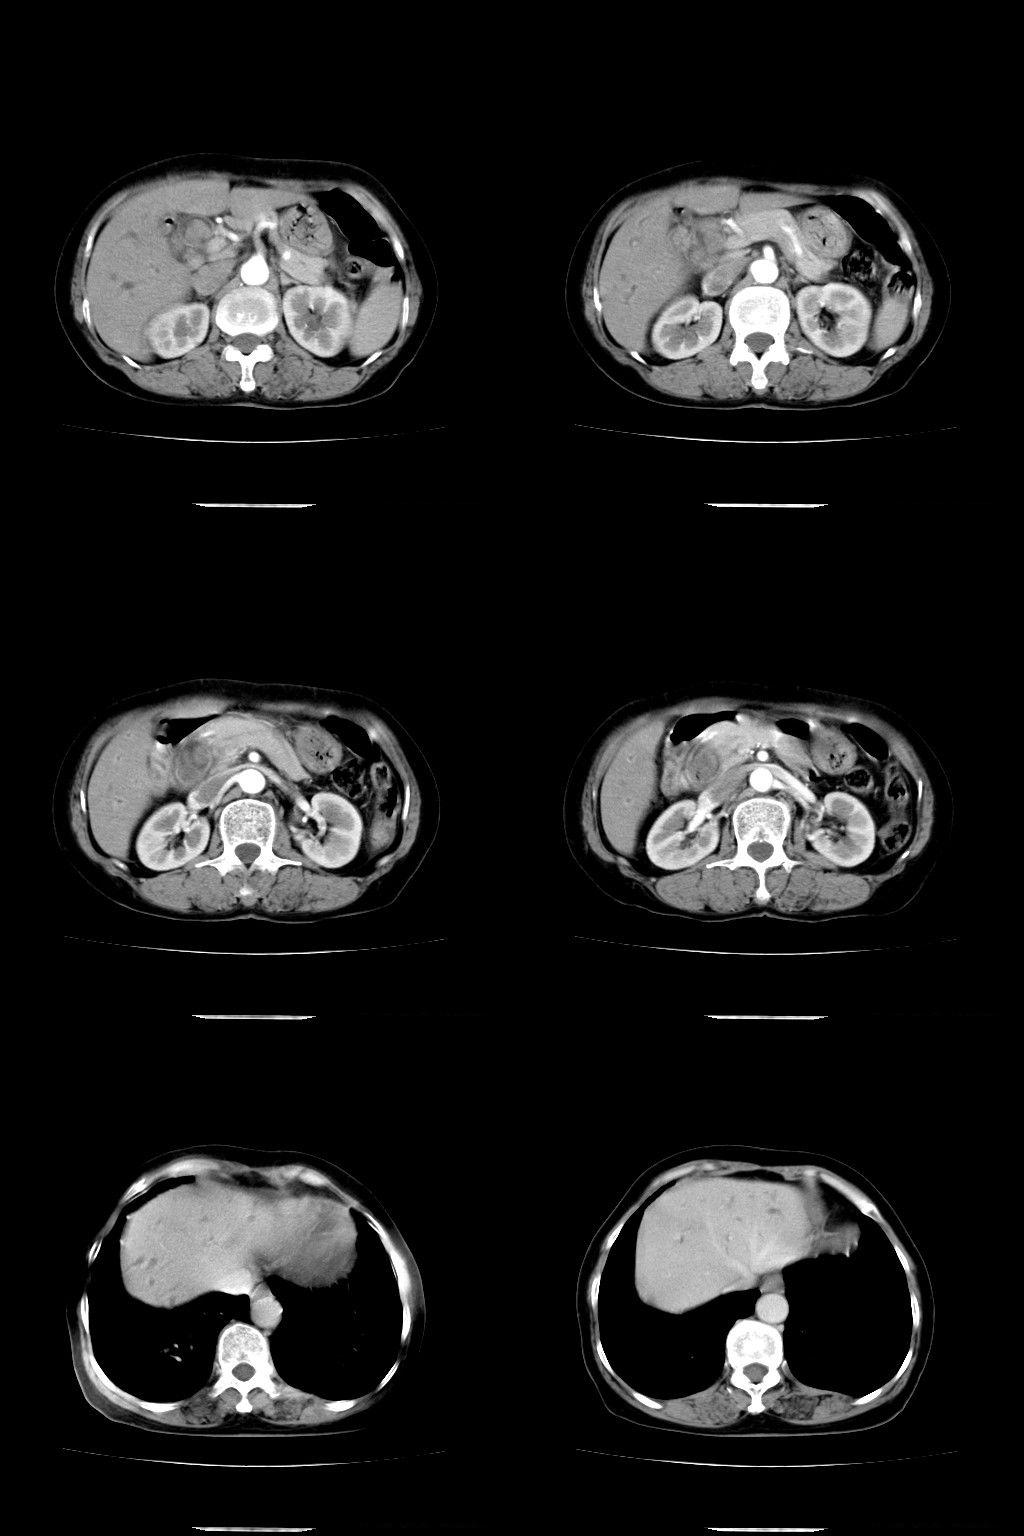

以下是引用余辉在2009-1-22 8:49:00的发言:[br]平扫肝内胆管扩张,右肝前叶球形低密度影,边缘较清楚,胆囊壁增厚,内可见较大高密度影,胆总管内亦可见高密度影,胰头区结构欠清。[br]增强动脉期见右肝前叶球形变灶明显增强,边缘见环状低密度区。胆囊见高密度影无增强,胆总管明显扩张,内见块状高密度影,周围环以低密度区,边界清楚。[br]静脉期见右肝前叶病灶持续增强,密度较动脉期增高。[br]考虑1胆囊及胆总管结石伴梗阻性胆系扩张,胆囊胆管炎。[br] 2右肝前叶占位性病变,强化规律符合胆管细胞癌,建议结合其他检查协诊